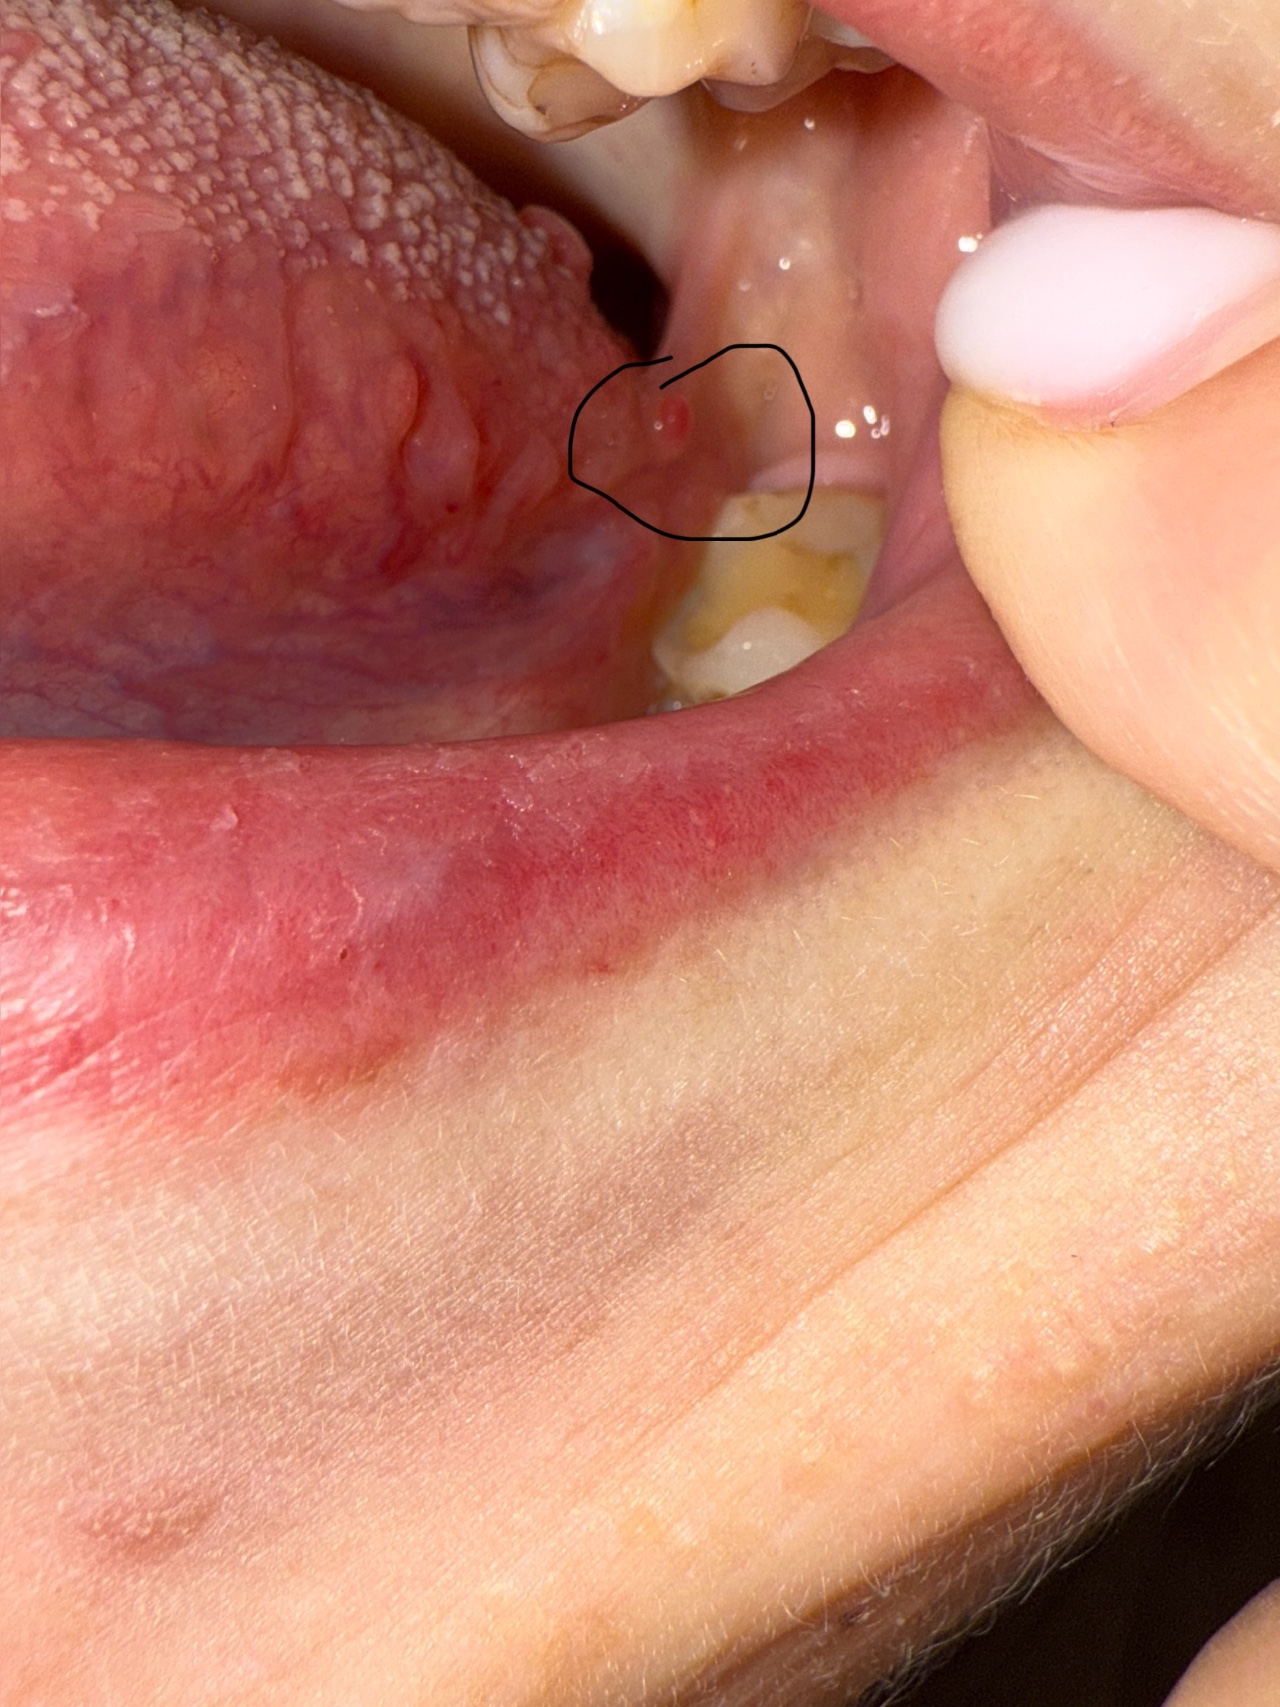

Выпуклость на небной дужке

ЭЗдравствуйте, что это за образование на небной дужке? Была на приеме у онаолога-хирурга, мне сказали, что это сиалоденит. На втором и третьем фото, когда язык в бок сдвигаю, это образование получается на корне языка.